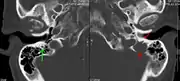

The diagnostic examination of a person with suspected multiple myeloma typically includes a skeletal survey. This is a series of X-rays of the skull, axial skeleton, and proximal long bones. Myeloma activity sometimes appears as "lytic lesions" (with local disappearance of normal bone due to resorption). And on the skull X-ray as "punched-out lesions" (raindrop skull). Lesions may also be sclerotic, which is seen as radiodense.[52] Overall, the radiodensity of myeloma is between −30 and 120 Hounsfield units (HU).[53] Magnetic resonance imaging is more sensitive than simple X-rays in the detection of lytic lesions, and may supersede a skeletal survey, especially when vertebral disease is suspected. Occasionally, a CT scan is performed to measure the size of soft-tissue plasmacytomas. Bone scans are typically not of any additional value in the workup of people with myeloma (no new bone formation; lytic lesions not well visualized on bone scan).

A CT of the brain revealed a lytic lesion in the left temporal bone (right side of image), and petrous temporal bones involving the mastoid segment of the facial nerve canal. Red arrows: lesion; green arrow: normal contralateral facial nerve canal. The lesions are consistent with a myeloma deposit.